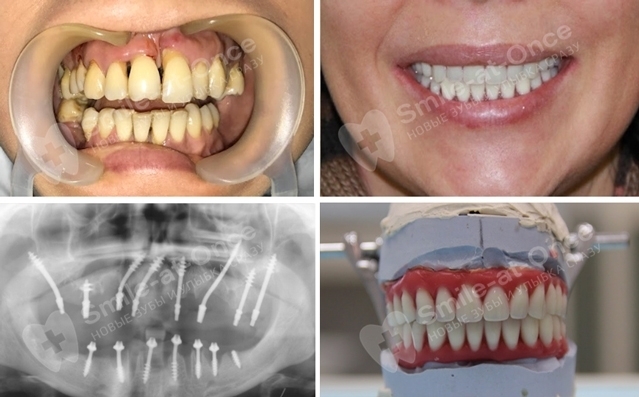

Еще одна общая черта всех методов — само протезирование. Оно делится на два этапа: сразу после вживления имплантатов устанавливают несъемный адаптивный протез. Он имеет металлический базис, который обеспечивает жесткость всей системы (за счет соединения всех имплантатов достигается их стабилизация и неподвижность). Протез выполнен из акриловой пластмассы, которая скрывает неровности слизистой, а также пластмассовых коронок с добавлением алмазной крошки. Пластмасса не идеальный вариант для протезирования, однако в случае немедленной нагрузки именно она придает протезу легкость и возможность корректировки. Протез не перегружает имплантаты и может подвергаться корректировке прямо во рту.

Адаптивный протез нужно носить не менее полугода — все то время, пока имплантаты и кость срастаются. Но в действительности он полноценно прослужит около 3–5 лет (за счет алмазной добавки прочность и эстетика материала в разы выше обычного протеза из акрила). После его можно заменить на постоянную конструкцию, срок службы которой уже исчисляется десятилетиями — протез также будет выполнен с небольшой частью искусственной десны, либо можно провести хирургическую пластику слизистой и оставить только коронки. Они могут быть созданы из металлокерамики или диоксида циркония.